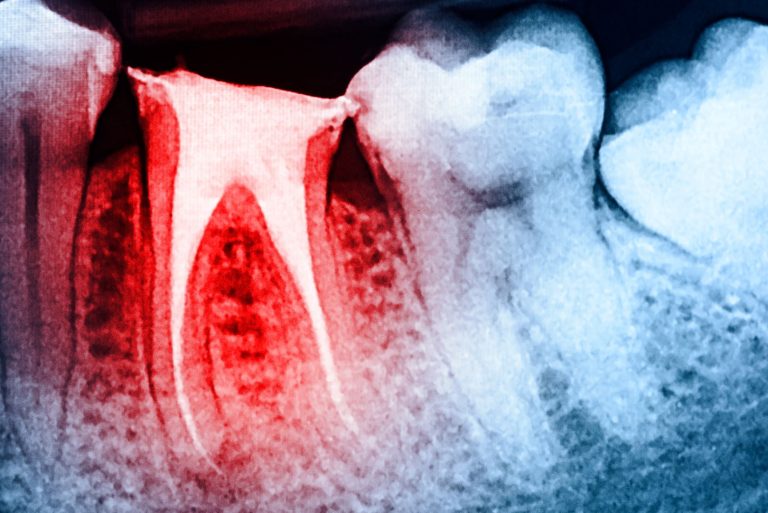

During your dental visit, your dentist will examine your teeth and gums, check for signs of oral cancer, and clean your teeth. They may also take X-rays to identify any underlying issues.